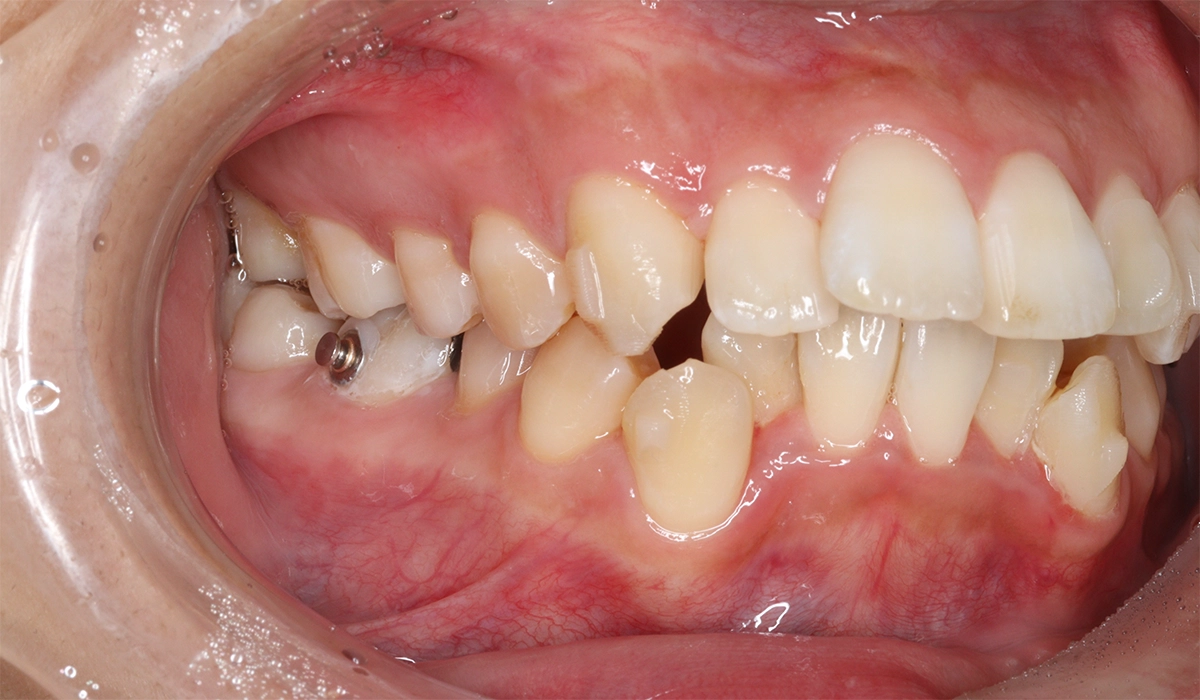

術前:左側